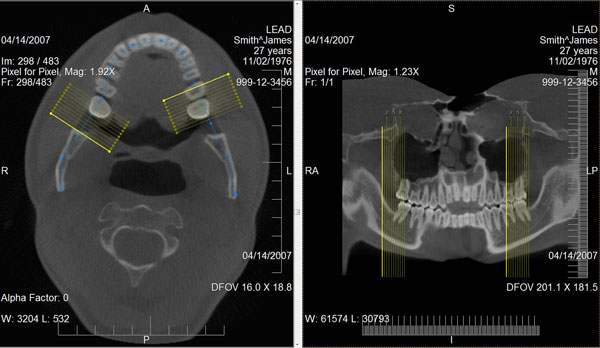

通过使用先进的视角分析算法将弯曲的部分投影到一个平面上,曲面多平面重组可从一堆二维切片中生成二维的全景影像和近轴切影像。曲面多平面重组的使用在牙科和断层扫描(ct)专家中非常流行,他们需定期检查具有弯曲几何的骨骼,如牙齿和血管。

leadtools medical image viewer控件支持曲面多平面重组功能,允许开发者将此功能无缝的添加到他们的应用程序中。medical viewer控件提供了交互式的工具,可以绘制曲线、移动全景点、生成全景影像、自动创建近轴线和生成近轴影像。结果影像可和影像分析工具一起使用,如window/level,alpha,平移、缩放、滚动和测量。它还提供了影像处理和标注的工具。